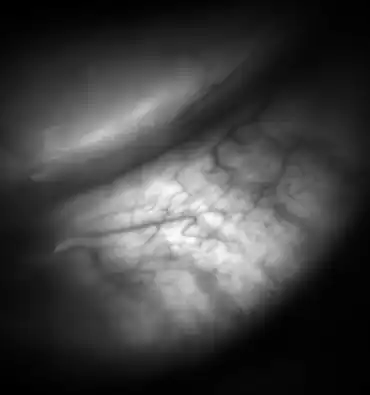

| Meibomian glands in the lower eyelid imaged under amber light to show vasculature support and the gland structure. | |